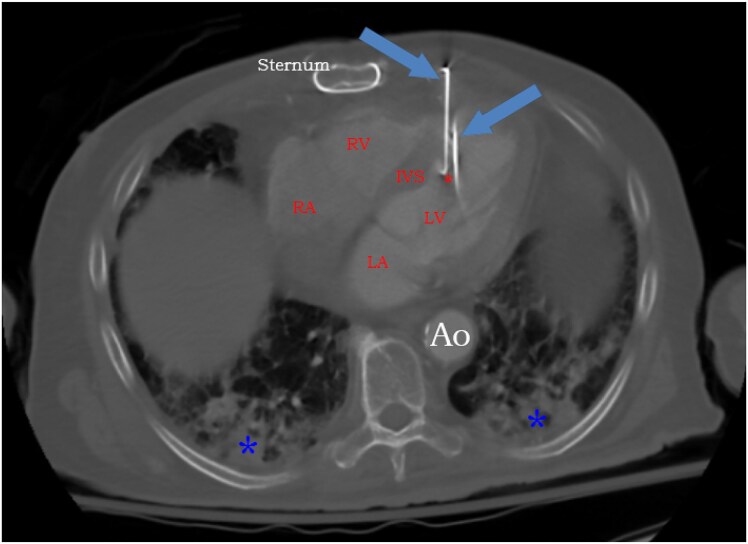

Case summary: A frail 83-year-old male who had undergone coronary artery bypass grafting surgery 20 years ago presented with encephalopathy. He had persistent bacteraemia. Chest computed tomography revealed three metal nails penetrating the anterior thoracic wall through the myocardium. Later, we learned that he had attempted suicide 2 years ago by shooting himself in the chest using a nail gun. Conservative non-surgical approach was pursued at that time given his multiple comorbidities. We adopted a conservative approach again. He survived for additional 6 months on chronic suppressive antimicrobial therapy but ultimately passed away from pneumonia.